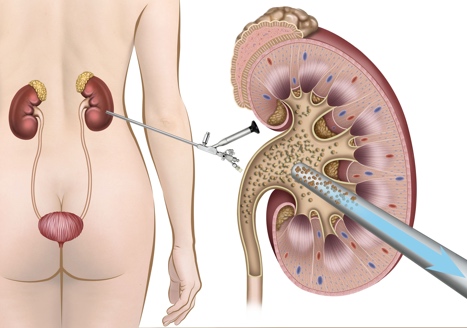

Ουρητηροσκόπηση

Αυτή η επέμβαση χρησιμοποιείται για τη θεραπεία λίθων μικρού έως μεσαίου μεγέθους που βρίσκονται στους νεφρούς και τους ουρητήρες.

Η ουρητηροσκόπηση (Εικ. 2), γίνεται χωρίς τομή στο δέρμα, καθώς τα χειρουργικά εργαλεία περνούν μέσα από την ουρήθρα και την φυσιολογική αποχέτευση του ουροποιητικού συστήματος. Η επέμβαση πραγματοποιείται είτε υπό γενική είτε υπό ραχιαία αναισθησία.

Ο ουρολόγος χρησιμοποιεί ένα λεπτό, εύκαμπτο σωλήνα που ονομάζεται ουρητηροσκόπιο και εισάγεται μέσω της ουρήθρας στην ουροδόχο κύστη, στην συνέχεια στον ουρητήρα και τελικά στο νεφρό. Ο λεπτός αυτός σωλήνας έχει μια μικροσκοπική κάμερα στο άκρο του που χρησιμοποιείται για τον εντοπισμό των λίθων. Τα χειρουργικά εργαλεία (Εικ. 3) όπως η λαβίδα σύλληψης και το basket, περνούν μέσα από ένα ειδικό κανάλι εργασίας του ουρητηροσκοπίου, έτσι ώστε ο γιατρός να μπορεί να αφαιρέσει τυχόν μικρές πέτρες.

Εάν υπάρχουν μεγαλύτερες πέτρες, ο ουρολόγος θα περάσει μια λεπτή ίνα λέιζερ στο εσωτερικό του ουρητηροσκοπίου για να θρυμματίσει τις πέτρες σε μικρότερα κομμάτια τα οποία μπορούν στη συνέχεια να αφαιρεθούν, ή να αφεθούν στη θέση τους, αν είναι πολύ μικρά, ώστε να περάσουν δια της αποχετευτικής οδού, φυσιολογικά κατά την ούρηση.

Μετά τη ουρητηροσκόπηση, μπορεί να χρειαστεί να τοποθετηθεί ένα στέντ (ένας μικρός σωλήνας σιλικόνης) για να κρατήσει τον ουρητήρα ανοιχτό έτσι ώστε να εξασφαλιστεί ότι τα ούρα θα μπορούν να παροχετεύονται ελεύθερα. Αυτά τα στέντ είναι προσωρινά και αφαιρούνται εύκολα μερικές εβδομάδες μετά την επέμβαση.

Εικ. 2: Η εύκαμπτη Ουρητηροσκόπηση

Εικ. 3: Αφαίρεση λίθου με την χρήση ενός basket